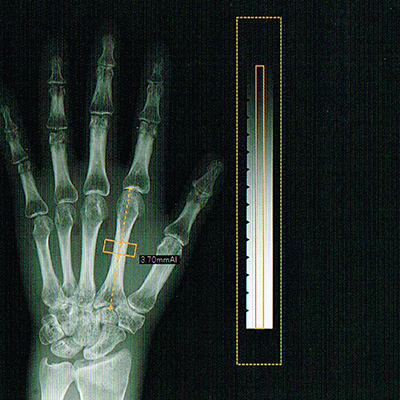

骨粗しょう症について診断するための検査です。

当院では両手のレントゲンによる検査を行っています。